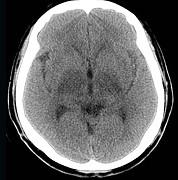

问题 男,57岁,头痛、头晕1周,言语不清,饮水呛咳两天,既往有鼻咽癌病史,给予放射治疗,CT检查如图所示,最可能的诊断为()

选项 A.脱髓鞘病变 B.脑炎 C.放射性脑病 D.脑梗死 E.胶质瘤

答案 C